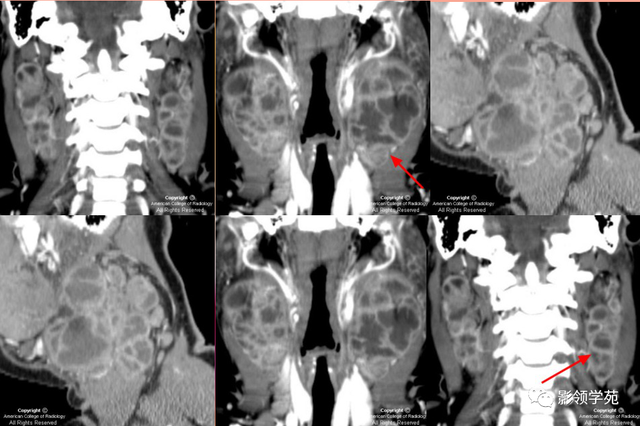

1.囊肿:分为潴留性和先天性两大类,先天性囊肿分皮样囊肿和鳃裂囊肿两大类。CT体现为囊性低密度肿块,T1WI呈低信号,T2WI呈高信号,增强扫描无强化